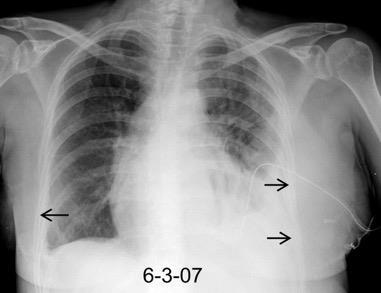

Masa axilar izquierda y derrame pleural derecho. Implantes pleurales, paraespinales . Ganglios en mamaria interna. Linfoma B difuso